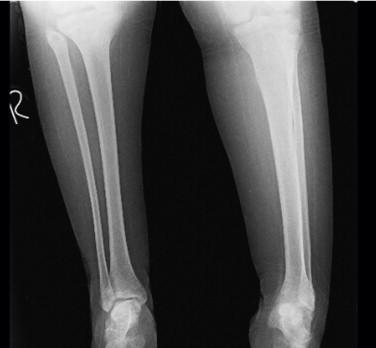

Serratia marcescens is an unexpected pathogen for subacute osteomyelitis in adolescence. Because of difficulty of diagnosis, treatment can be delayed or cause complications like nonunion or loss of function. We present a meningomyelocele female adolescent operated with distal tibia varus osteotomy for correcting ankle valgus deformity. Insufficient healing was determined at osteotomy side on radiographs. The patient's erythrocyte sedimentation rate and CRP level was slightly higher with minimal clinical inflammation. MRI examination showed abscess formation at T2 imaging. Debridement, grafting and circular external fixation was performed. Sulperazon was started for drug therapy. Union was achieved after compression and distraction osteogenesis by circular external fixator. Orthopedic surgeons should be aware of opportunistic infections like serratia and keep in mind as a probable cause of disease.

粘质沙雷氏菌是青少年亚急性骨髓炎中一种意想不到的病原体。由于诊断困难,治疗可能会延迟或导致诸如骨不连或功能丧失等并发症。我们报告一名患有脊髓脊膜膨出的女性青少年,她接受了胫骨远端内翻截骨术以纠正踝外翻畸形。X线片显示截骨部位愈合不佳。患者的红细胞沉降率和CRP水平略有升高,临床炎症轻微。MRI检查在T2成像上显示有脓肿形成。进行了清创、植骨和环形外固定。开始使用舒普深进行药物治疗。通过环形外固定器进行加压和牵张成骨后实现了骨愈合。骨科医生应意识到像粘质沙雷氏菌这样的机会性感染,并将其作为可能的病因牢记在心。